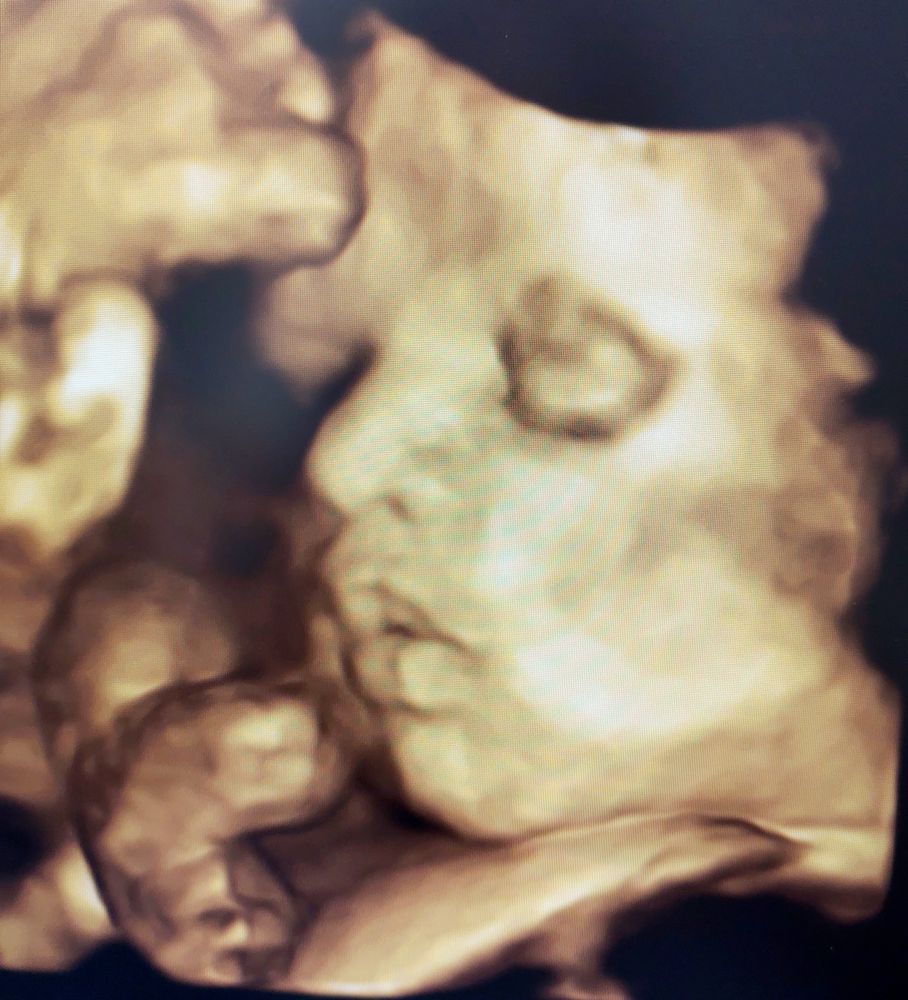

Швы сняты! 38 недель кровотечение